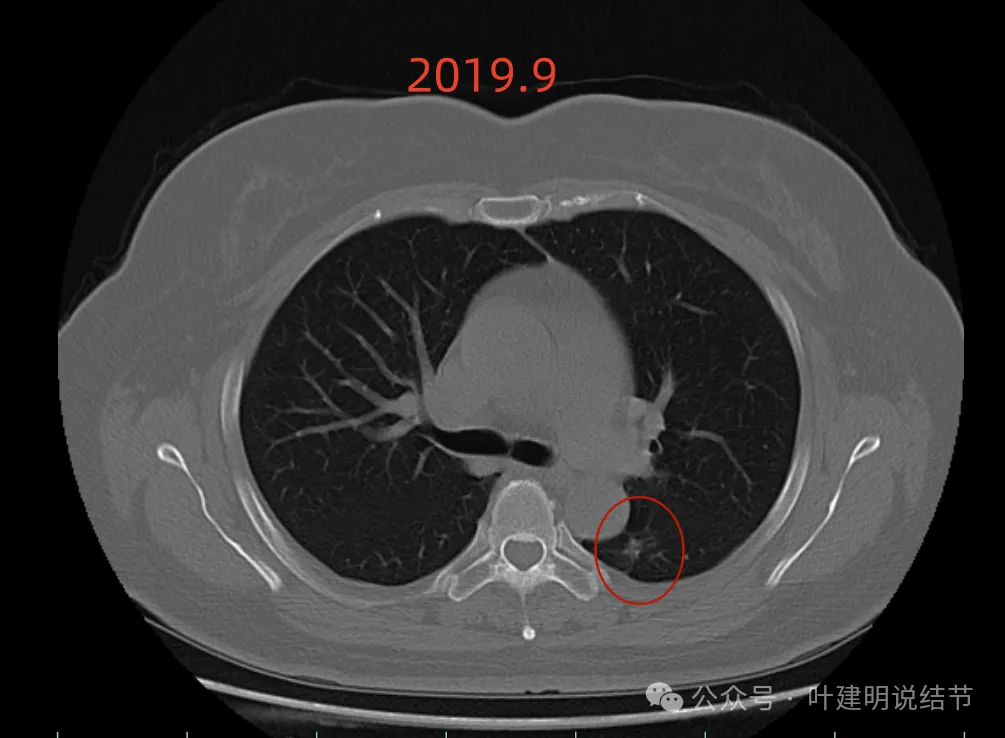

先看2019年时的影像:

病灶出现,密度不纯,有点状高密度成分,表面不光滑不平整。

实性成分为主,但边缘缺乏膨胀性,长刺较细长,感觉更像慢性炎。

此层不是很像炎症,有一定膨胀性。黄色箭头处示有细支气管被病灶截断似的;紫色箭头示略有小的毛刺征;但绿色箭头所指的胸膜有增厚的表现,而且蓝色箭头指的条状不锐利,这又与炎性病变并影响邻近胸膜是符合的。